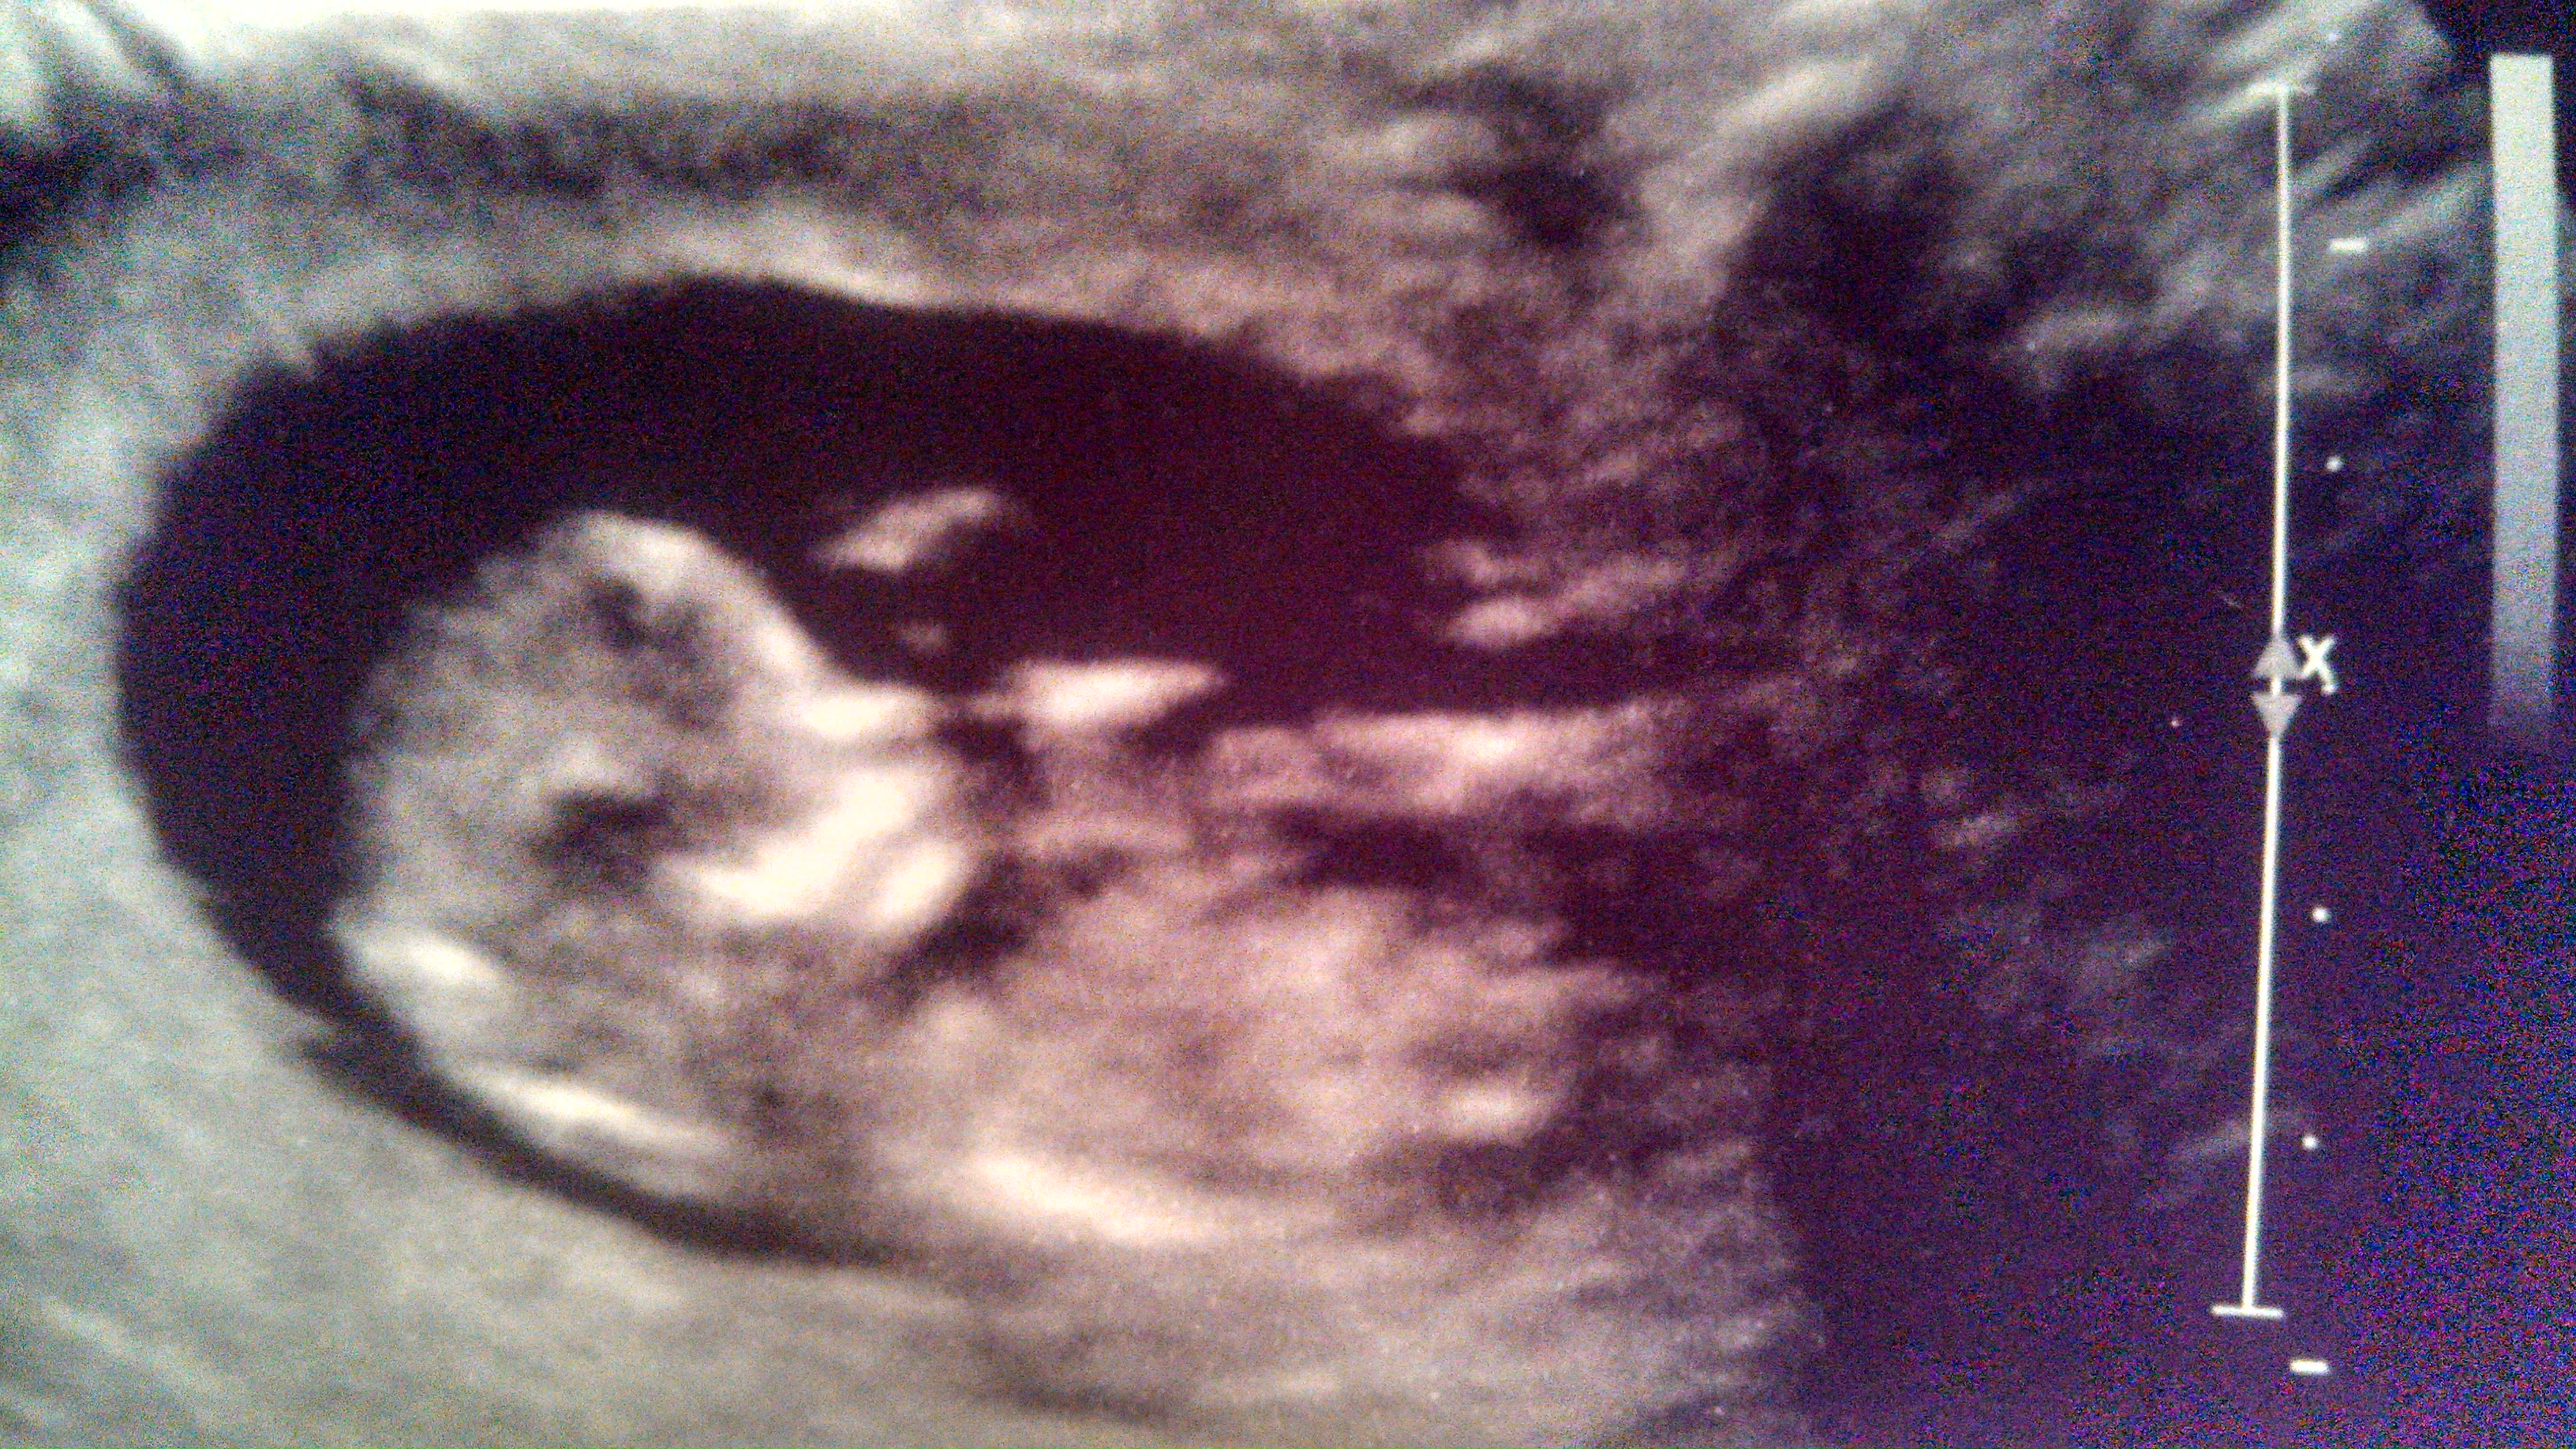

I really think the 3rd time's the charm and our GIRL gender sway worked after 2 beautiful boys. Nub/skull pics are from 13 weeks. Please make my day with some input, thanks :)

I'm not 100% sure that's the nub....sorry I can't make a good guess....fingers crossed it's your pink bundle x

I'm sorry if thats the nub I would Actualy lean to boy. But I find it hard to see.

I agree with Sweetdream it's pretty angled I would say boy I hope we are wrong

I hate to say it but I agree that I'd lean boy. There is an angle to the nub looking at the spine and the shadow on top that could be a stacked nub is esp what makes me think boy. Either way you have a very cute baby!

I hate to say this but it could go either way, but I would have to lean boy if I must guess.

The truth is though, you don't have a good image of the nub itself (the end). Its very blurry. I think I could more accurately guess if the nub was clear.

The only reason I slightly lean boy is because the shaft part is slightly angled because it has risen slightly from the body. Usually girl nubs (even if they looked slightly angled) have not risen from the body -- there is no black space under the shaft part.

I agree I don't think that's the nub circled but hope you hear pink xx